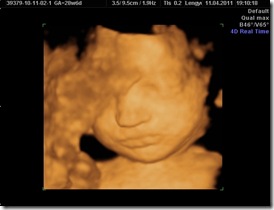

Pici babánk nagyon jól érzi magát, 29 hetesen már 1500g a súlya és következzenek a sztárfotók.

Imádnivaló kis gyönyörűség ő is mint a nővére. <3